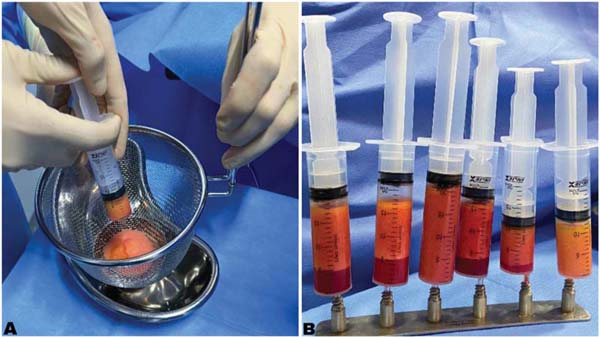

In the filtration group, adipose tissue was processed through a 16-cm stainless steel sieve. In the decantation group, the tissue was placed in vertical syringes and allowed to sit for 20 minutes. This process relied on gravity to separate adipose tissue components, that is, solids (fat) and liquids (oil, serum, saline solution). Next, the serum and oil separated from the fat were discarded, leaving only the fat ready for transplant.

The filtered or decanted fat was transferred to 3-mL or 10-mL syringes using 2-way stainless steel transfer devices. Next, fat was infiltrated into the breast through a small incision with simple single-hole cannulas (2 mm in diameter and 200 mm in length), establishing tunnels for fractional retroinjection into the subcutaneous tissue of the areas requiring correction (►Fig. 4).